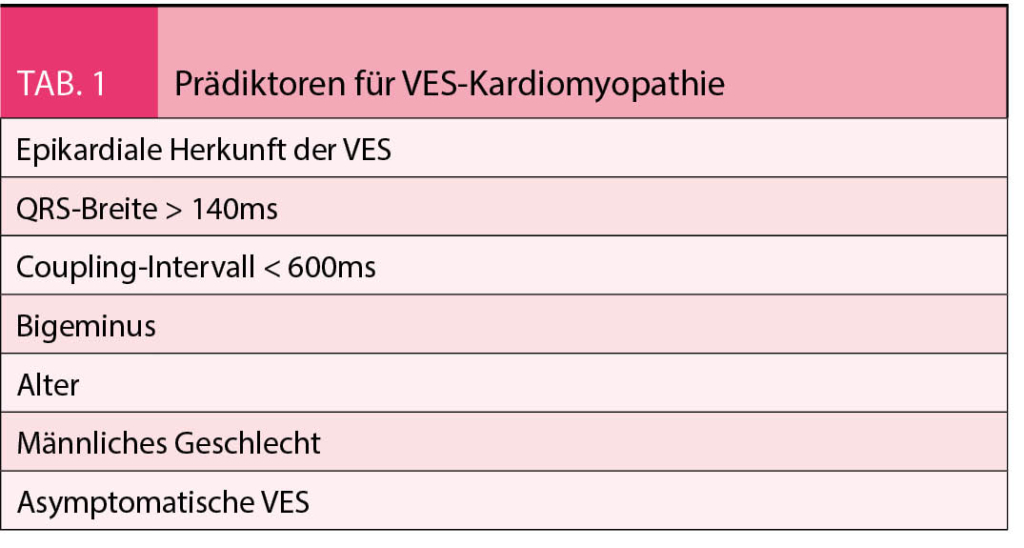

Für Patienten mit struktureller Herzerkrankung oder Herzinsuffizienz ist eine Assoziation von gehäuften VES mit erhöhter Morbidität und Mortalität hinreichend bekannt (17-20). Retrospektive Daten zeigen aber auch für herzgesunde Patienten mit VES ein signifikant höheres Risiko für die Entwicklung einer Herzinsuffizienz, unabhängig von kardiovaskulären Risikofaktoren und mit proportional zur VES-Häufigkeit ansteigendem Risiko (21). Das Konzept einer durch VES induzierten Herzinsuffizienz wurde erstmals 1998 postuliert, basierend auf der Normalisierung der LVEF nach medikamentöser Suppression der ventrikulären Extrasystolie (22). Im Anschluss zeigten mehrere Fallserien mit Patienten ohne strukturelle Herzerkrankung aber gehäuften VES (meist > 10 000/24h) nach erfolgreicher Radiofrequenzablation (RFA) der VES eine Verbesserung der LVEF, der kardialen Dimensionen und klinischen Parameter (23-27). In den nachfolgenden Jahren konnte auch eine Verbesserung der LVEF nach RFA bei vorbestehender ischämischer oder nicht-ischämischer Herzerkrankung und erst sekundär aufgetretener VES nachgewiesen werden (28-30). Die daraus resultierende kontroverse Diskussion, ob VES bei Patienten mit struktureller Herzerkrankung nur Ausdruck letzterer sind oder einen kausalen Bestandteil der Kardiomyopathie darstellen, dauert bis heute an (31). Immerhin ist mittlerweile bekannt, dass sich der positive Effekt einer erfolgreichen VES-RFA auf die LVEF und Herzinsuffizienz-Symptomatik unabhängig der zugrundliegenden Erkrankung auswirkt (32, 33). Bis zu 50% aller Patienten mit ätiologisch unklarer HFrEF und relevanter ventrikulärer Extrasystolie scheinen dabei eine rein VES-induzierte Kardiomyopathie mit kompletter Normalisierung der LVEF nach erfolgreicher RFA aufzuweisen, während bei den anderen «nur» eine Verbesserung ohne Normalisierung der LVEF erzielt werden kann im Sinne einer durch VES akzentuierten Kardiomyopathie (34). Diese reproduzierbaren Beobachtungen prägten die aktuelle «Definition» einer VES-assoziierten Kardiomyopathie: eine linksventrikuläre Dilatation und eingeschränkte LVEF mit oder ohne zugrundeliegende strukturelle Herzerkrankung bei Patienten mit gehäuften VES und Besserung der linksventrikulären Dysfunktion nach pharmakologischer oder interventioneller Suppression der VES (35). Die linksventrikuläre Funktion scheint proportional mit dem VES-Burden abzunehmen (36), eine absolute Grenze mit sicherer Prädiktion für die Entwicklung einer VES-induzierten Kardiomyopathie existiert aber nicht; Anhand verschiedener retrospektiver Analysen wurden unterschiedliche Grenzwerte (> 10% Burden, > 24% Burden, > 10 000 VES/24h) vorgeschlagen (36-38). Interessanterweise tritt bei den einen Patienten mit sehr hohem VES-Burden keine Kardiomyopathie auf, während andere Patienten mit vergleichsweise wenig VES eine linksventrikuläre Dysfunktion entwickeln. Dies suggeriert eine individuelle Suszeptibilität der Entwicklung einer VES assoziierten Kardiomyopathie, welche aktuell noch unklar ist – bekannt sind bisher einige Patienten- und VES-spezifische Einflussfaktoren (Tab. 1) (24, 39, 40).